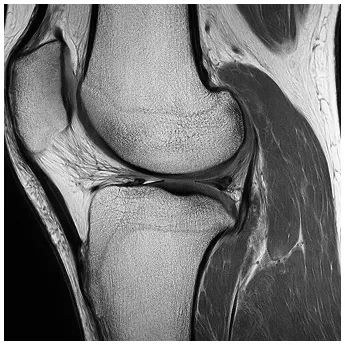

診断

半月板損傷かどうかを調べるには、膝の動きや痛みの出方を確認するいくつかの徒手検査があります。代表的なものとして、ApleyテストやMcMurrayテスト、膝を過伸展させるHyperextensionテストなどがあります。また、膝の押したときの痛み(圧痛)も診断の手がかりになります。

半月板はレントゲンでは見えないため、詳しく状態を確認するにはMRI検査が必要です。MRIを使うことで、損傷の形や範囲を正確に把握でき、適切な治療方法を決める際に非常に役立ちます。

MRI

半月板が水平に断裂している様子を示したMRI写真